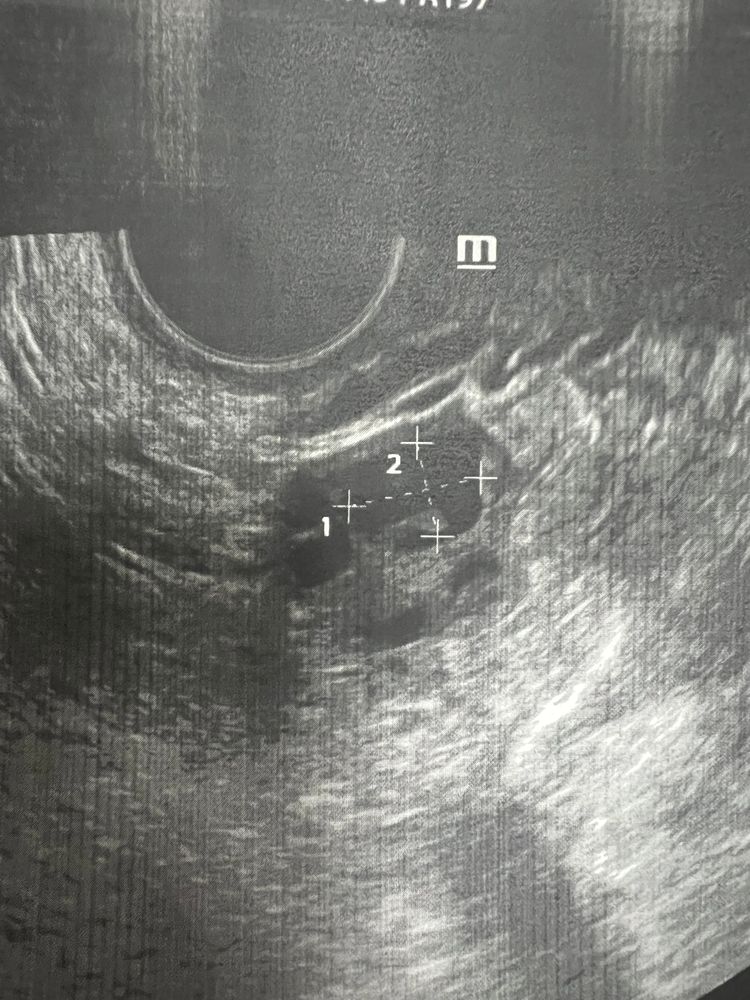

На узи фоликуламетрии киста жт уменьшилась с 5см до 1см но внутри смущает какой то отросток так сказать…. Что это может быть у кого было так!? Это киста такая или внематочная ичниковая беременность или опухоль какая то! Не понятно! Врач и узи будет только в пятницу, может кто то что то скажет, кто сталкивался с таким!🫣

До этого была киста жт 5 см сейчас 1 см….и вот узи! Непонятно что и как!?😅 врач предполагает что это может выпал фибрин (как я поняла сгусток крови), завтра все ясно будет что у меня там такое!:)